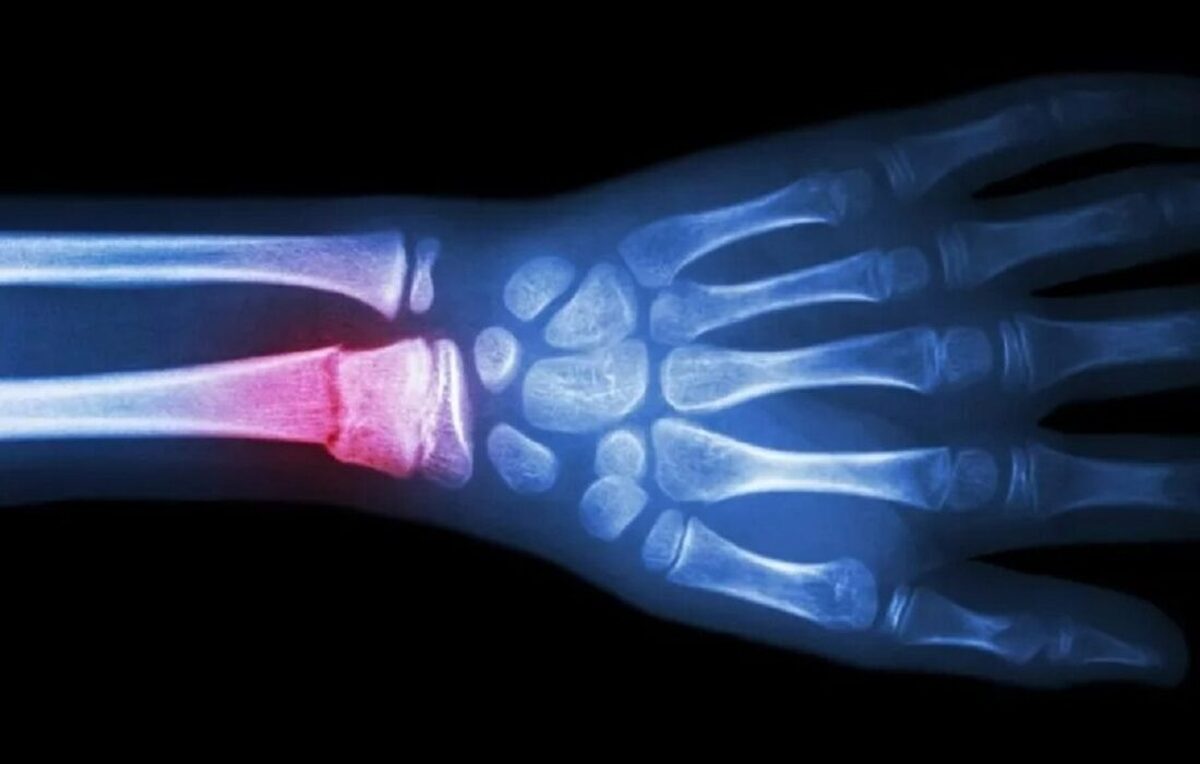

روشی سریع و مقرون‌به‌صرفه‌تر برای ترمیم استخوان شکسته ارائه شد!

محققان در کره جنوبی در جستجوی گزینه‌ای سریع‌تر و مقرون‌به‌صرفه‌تر برای ترمیم استخوان شکسته، به توسعه روشی پرداختند که می‌تواند ایمپلنت‌های استخوانی مخصوص بیمار را بدون هزینه‌های بالا یا سرعت پایینِ روش‌های سنتی موجود ایجاد کند. محققان در کره جنوبی در جستجوی گزینه‌ای سریع‌تر و مقرون‌به‌صرفه‌تر برای ترمیم استخوان شکسته، به توسعه روشی پرداختند که می‌تواند ایمپلنت‌های استخوانی مخصوص بیمار را بدون هزینه‌های بالا یا سرعت پایینِ روش‌های سنتی موجود ایجاد کند.

به گزارش مجله خبری نگار/برنا، پیوند فلز و ایمپلنت‌های مبتنی بر تیتانیوم همچنان جزء روش‌های استاندارد تثبیت شکستگی‌های شدید استخوان به شمار می‌رود، اما تولید آنها گران است و سفارشی‌سازی آنها برای هر بیمار دشوار است. این در حالی است که اگرچه چاپ سه‌بعدی دری را به روی راه‌حل‌های شخصی‌سازی‌شده‌تر باز کرده است، اما هنوز به زمان و منابع قابل توجهی نیاز دارد. به همین دلیل محققان دانشگاه سونگ کیون کوان در کره جنوبی، در جستجوی گزینه‌ای سریع‌تر و مقرون‌به‌صرفه‌تر، به توسعه روشی پرداختند که می‌تواند ایمپلنت‌های استخوانی مخصوص بیمار را بدون هزینه‌های بالا یا سرعت کم روش‌های سنتی ایجاد کند.